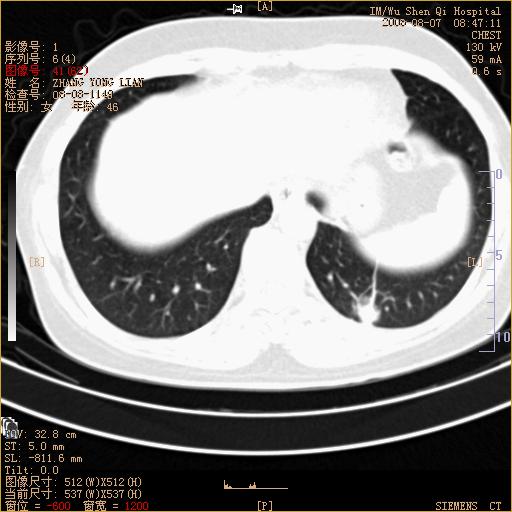

标题: CT15050:女,46岁,咳嗽胸痛一月余 [打印本页]

纵隔窗没发全,左下肺近胸膜处结节。有长毛刺,纵隔淋巴结增大,不排除恶性病变。

考虑肺癌

考虑左肺下叶后基底段周围型肺癌伴纵隔淋巴结转移可能性大。

左下肺ca并纵隔及左肺门区淋巴结转移。

脾脏低密度结节转移不排除。

1)考虑左肺下叶后基底段周围型肺癌伴纵隔淋巴结转移。2)脾内低密度灶,性质待定;不排除转移瘤可能。

考虑左肺下叶后基底段周围型肺癌伴纵隔及肺门淋巴转移。